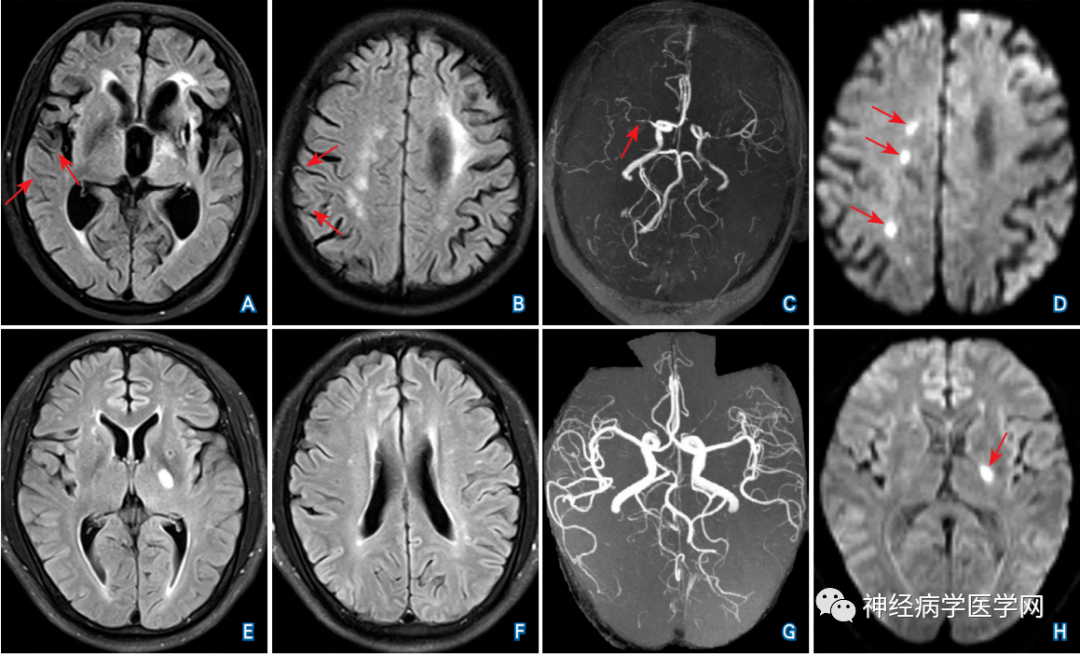

t2 flair序列未见责任病灶确切显影,呈dwi-flair不匹配.

ajnr:mca闭塞远端flair血管高信号征是好现象还是坏现象?

flair高信号血管征在dwi不同梗死分型中与临床预后的关系研究